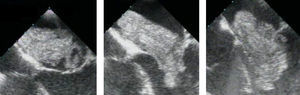

Sequência (a partir de vídeo-imagens de ecocardiografia transesofágica) do movimento diastólico de um volumoso mixoma sólido, com protrusão para o ventrículo esquerdo através do aparelho valvular mitral (com um movimento que imita o de um martelo-pilão), condicionando alterações valvulares estruturais e funcionais e provocando insuficiência mitral intermitente (sequência da esquerda para a direita).

Sequência (a partir de vídeo-imagens de ecocardiografia transesofágica) do movimento diastólico de um muito volumoso mixoma viloso, com protrusão para o ventrículo esquerdo através da válvula mitral, condicionando alterações valvulares estruturais e funcionais que determinam insuficiência mitral ligeira (sequência da esquerda para a direita).